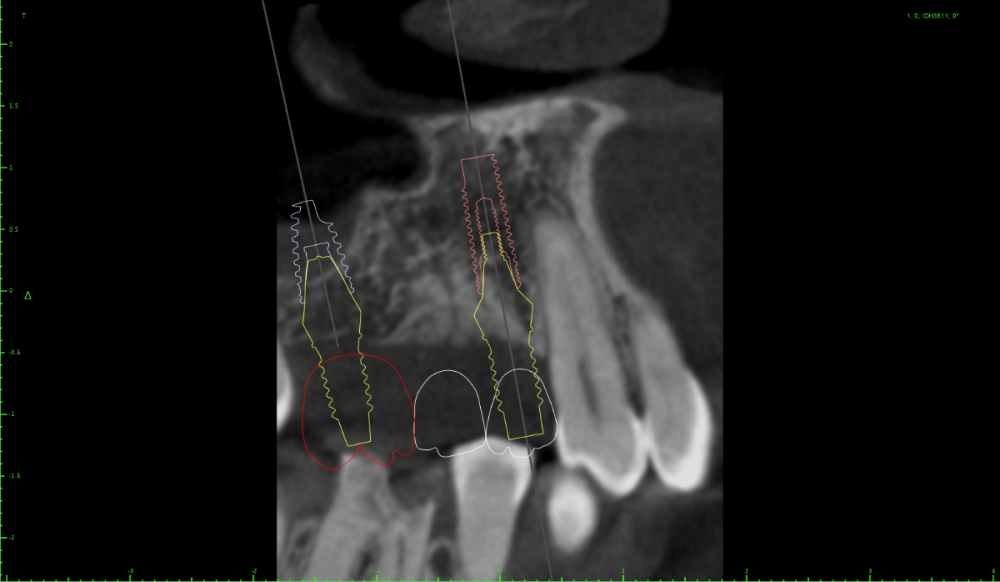

Женька Опубликовано 15 июля, 2022 Поделиться Опубликовано 15 июля, 2022 Коллеги, здравствуйте. Планирую небольшую НКР совместно с ОСЛ в боковом отделе верхней челюсти справа. Вот скрины. На реформате 3д план. Пожалуйста, поделитесь правильно ли мной выбран дизайн лоскута и фиксация мембраны (мембрана будет Creos, кость ауто+ксено (возможно ещё немного алло) p.s вариант обойтись без пластики не предлагать.)) Правильной ортопедической позиции добиться без нкр не выходит, кмк. Да и надо же пробовать как-то. Ссылка на комментарий

колесников Опубликовано 17 июля, 2022 Поделиться Опубликовано 17 июля, 2022 Во первых: у вас нет потери вертикального объёма,гребень практически в зените-это хорошо. Во вторых:вам нужно заглубить платформы имплантов. В третьих:складываемся первое и второе и получаем... ремоделировку на 2-3-4 мм . И вот у вас уже не такой критично узкий гребень. Зачем вам нкр? Для импланта? Нет,имплант в кости(Возьмите 3.5х6; 3.5х8) Для ортопедии? Ок. Проведите десневую аугментацию ,лоскутом с бугра. Или сделайте нкр по Штайгману поднадкостнично(если так хочется попрактиковаться в нкр). Или возьмите остеотом или трепаном бугор и зафиксируйте его винтом вестибулярно(если хочется применить винты). В четвёртых: зачем вам открытый синус и неясные перспективы? На снимке все будет выглядеть красиво,вы потешите своё чсв,а по факту импланты уйдут через 2 месяца после нагрузки. Сделайте 1 закрытый синус ,плюс все выше перечисленное и вы будете выглядеть виртуозом в глазах пациента,тк сделаете все в 1 этап и не травматично. В идеале можно (Нужно) даже нагрузить. 3 Ссылка на комментарий

Женька Опубликовано 18 июля, 2022 Автор Поделиться Опубликовано 18 июля, 2022 (изменено) @колесников штайгмана не умею, увы. открытый для меня более прогнозируем нежели закрытый. А вариант idr пока более сложен в исполнении для меня. Плюс в арсенале нет плоскостного соединения, только конус. Снова встаёт вопрос о правильных позициях ортопедических. Либо правильно это когда практически перпендикулярно стоит имплантат к окклюзионной плоскости ( небольшая ангуляция не критично) либо мы ставим по имеющейся кости, наклоняя платформу в вестибулярную сторону, но уходим от нкр. не понимаю я этого никак, где же правильность? Изменено 18 июля, 2022 пользователем Женька 1 Ссылка на комментарий

Женька Опубликовано 19 июля, 2022 Автор Поделиться Опубликовано 19 июля, 2022 @колесников считаете что надо именно так и обойтись без сосиджов? Мне кажется, что всё-таки более правильная позиция вот такая. . Касаемо ЗСЛ и одномоментной имплантации. Торкнуть конечно бикортикально можно, но глубить всё равно нужно. Я 4 месяца назад так поставил уже, теперь проблемы с высотой, которые я не знаю как решить пока (самое печальное, что сам же дурень создал их себе). Поэтому мне проще воплотить ОСЛ в данном случае и отсрочено поставить винты. Одно чудо за один раз, как говорится. Ссылка на комментарий

Bier Опубликовано 21 июля, 2022 Поделиться Опубликовано 21 июля, 2022 19.07.2022 в 14:47, Женька сказал: Мне кажется, что всё-таки более правильная позиция вот такая . Касаемо ЗСЛ и одномоментной имплантации. Торкнуть конечно бикортикально можно, но глубить всё равно нужно. Я 4 месяца назад так поставил уже, теперь проблемы с высотой, которые я не знаю как решить пока (самое печальное, что сам же дурень создал их себе). Поэтому мне проще воплотить ОСЛ в данном случае и отсрочено поставить винты. Одно чудо за один раз, как говорится. Ну нет конечно, первая позиция значительно лучше. По поводу синуса - тут есть где заглубить. Вам решать. Ссылка на комментарий